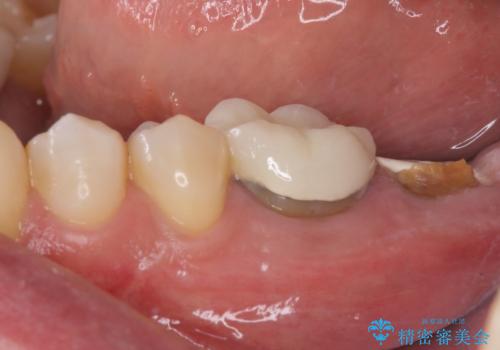

最後方歯であるため、入れ歯かインプラントかどちらかの補綴治療を行うこととなりますが、ご希望によりインプラント補綴治療を行うこととしました。

インプラントにはストローマン社のSLActiveを使用し、埋入から補綴までおよそ3か月と、短期間で治療を進めることができました。